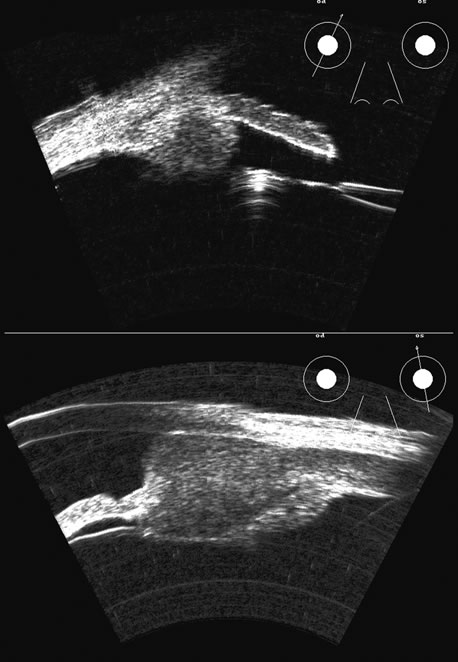

Fig. 17. This patient with a Molteno tube was treated for glaucoma. The top 50 MHz B-scan clearly shows the Molteno Tube (arrow). The bottom 10 MHz B-scan of the same patient demonstrates a choroidal detachment (large arrow) with associated posterior retinal detachment (small arrow). Choroidal elevations are typically convex, highly reflective surfaces with posterior limitation at the vortex vessels. Retina will always attach at the optic nerve. Choroidal elevations are often noted in several quadrants, as seen here.

The choroid, like the retina, is highly reflective and may resemble the retina when detached. Its thickness, which includes the retina, Bruch's membrane, and the choriocapillaris (tunica ruyschiana) is not usually differentiable when measured with routine ultrasound;12 however, it may be measured with digital techniques.18 Anatomically, the choroidal elevation is usually a smoothly round, convex surface, limited posteriorly by the vortex veins and anteriorly at any point up to the base of the iris (Fig. 17). The choroidal space should be examined for echoes (blood) or a clear zone, as seen with effusion or the serous part of a hemorrhage. In evaluating membranes from retina or choroid, it is always helpful to repeat the examinations at a later time.